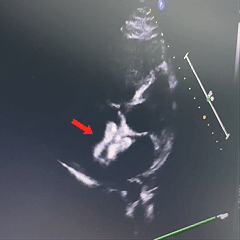

超声下确定封堵器左右两盘骑跨在房间隔两侧

超声下,封堵器结构稳定无散开,判断锁定成功

封堵器位置正确、夹持稳定、形态良好、无残余分流,封堵手术成功

沿房间隔可见封堵装置,沿其周围未测及残余分流。

超声提示:ASD封堵术后,无残余分流。

房间隔可见封堵器回声,位置固定,形态良好。房水平未见残余分流信号。

术后即刻超声检查显示封堵器位置正确、形态良好、夹持稳定,无残余分流。术后第1天和第2天的随访超声进一步显示房间隔可见封堵器回声,位置固定,形态良好,且房水平未见残余分流信号。